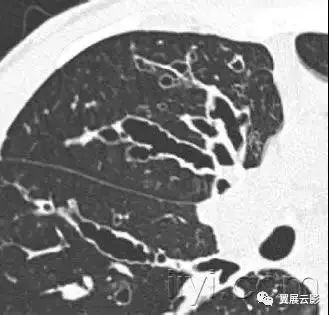

三十九、马赛克征

CT:本征象表现为不同的密度成片状镶嵌,可为间质性病变、闭塞性小气道病变(图)或者血管阻塞性疾病。马赛克征比马赛克样少血或者低灌注具有更强的诊断含义。由于支气管或细支气管阻塞导致的空气滞留可以导致局部的密度减低,在呼气相CT上表现更加明显。

该征象也可以见于间质性肺部疾病,特征是磨玻璃影,此时高密度代表间质性病变,低密度代表正常的肺。